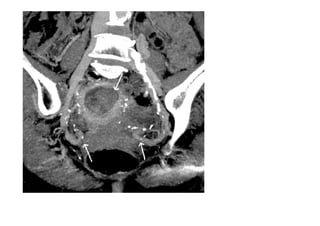

•  Examen  du  cas   d’une  pa=ente   traitée  pour  de   l’endométriose  par   chirurgie,  qui   con=nuait  a  avoir   une  conges=on   pelvienne.  L’examen   a  démontré  qu’elle   souffrait  également   de  varices   pelviennes.

• 35.